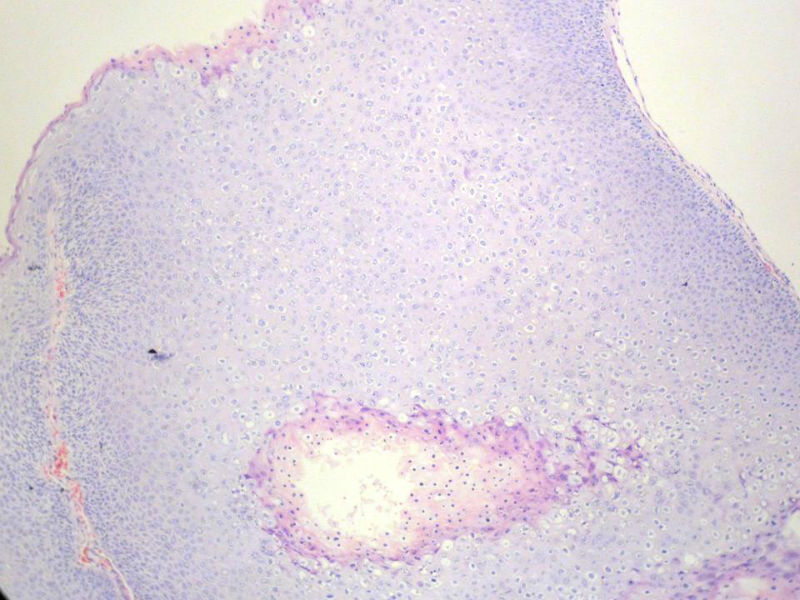

男,72岁,右耳听力下降两个月,检查右外耳道有黄豆大肿物,表面乳头状,手术切除。

乳头状瘤

乳头状瘤,有轻度异形,有恶变倾向

乳头状瘤,上皮内可见挖空样细胞,建议HPV检测

鳞状上皮乳头状瘤,未发现恶性变。